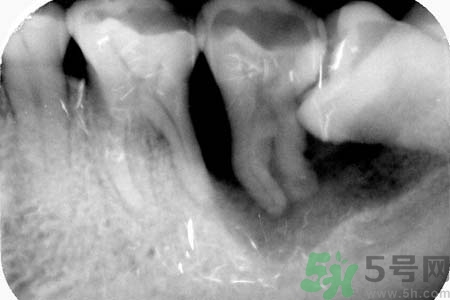

智齒能不拔嗎?智齒長在大家牙槽的最里面,比較不容易清潔干凈,還容易發(fā)炎。智齒還會(huì)影響人們的臉型,一般去醫(yī)院醫(yī)生都會(huì)建議拔掉智齒。關(guān)于智齒拔了好不好?智齒能不拔嗎?小編為您一一解答。

要不要拔智齒完全取決于大家的智齒長得怎么樣,事實(shí)上智齒和別的牙沒有質(zhì)的區(qū)別。只不過因?yàn)樗奈恢锰厥?,很容易長歪,而且在功能上又沒有特別的意義,所以醫(yī)生才建議拔掉。

智齒長在牙槽最里邊,平時(shí)清潔很難徹底,而且如果長歪了就更難清潔,所以就特別容易齲壞,慢慢發(fā)展成深齲,甚至感染導(dǎo)致炎癥膿腫等等。拔掉它只是為了絕后患,如果你的智齒長得好好的,就不要拔掉,畢竟拔牙是有創(chuàng)的手術(shù),會(huì)流血,而且24小時(shí)內(nèi)不能用那一邊吃東西,也挺麻煩的。拔牙一定要去正規(guī)醫(yī)院或診所,因涉及血液,胡亂去小攤可能因不慎感染肝炎或艾滋病。